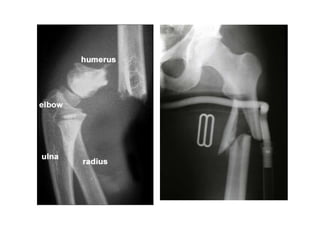

• humerus stress fracture in javelin thrower

•related to muscle trying to accelerate a “resisting” bone (torque)

Stress Fractures